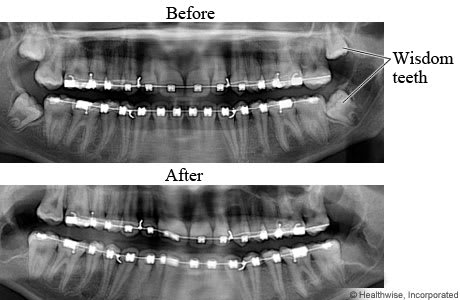

Wisdom teeth X-ray